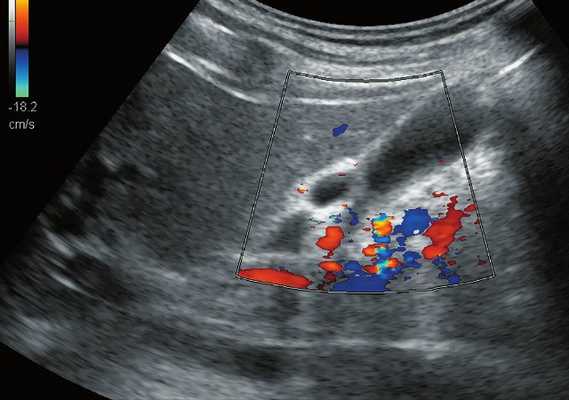

С подозрением на дивертикулит больная была направлена на срочное ультразвуковое исследование (УЗИ) органов брюшной полости, почек и органов малого таза. Исследование было выполнено на современном аппарате конвексным датчиком 3,5 МГц, линейным датчиком 7,5 МГц и эндовагинальным датчиком с переменной частотой 5,0-7,5 МГц с использованием цветового и энергетического допплеровского картирования.

При трансвагинальном УЗИ (рис. 4) также визуализировался фрагмент толстой кишки с утолщенными гипоэхогенными стенками и несколькими округлыми дивертикулами до 1 см в диаметре. Контуры одного из дивертикулов были неровными, он имел звездчатую форму. Отмечались утолщение и повышение эхогенности околокишечной жировой клетчатки по сравнению с контралатеральной стороной. При осмотре в режиме УЗ ангиографии утолщенная стенка кишки и дивертикулы были аваскулярными, окружающая клетчатка - гиперваскулярной.

Рис. 4. Эхографическая картина дивертикулита. Трансвагинальное исследование конвексным датчиком 7,5 МГц.